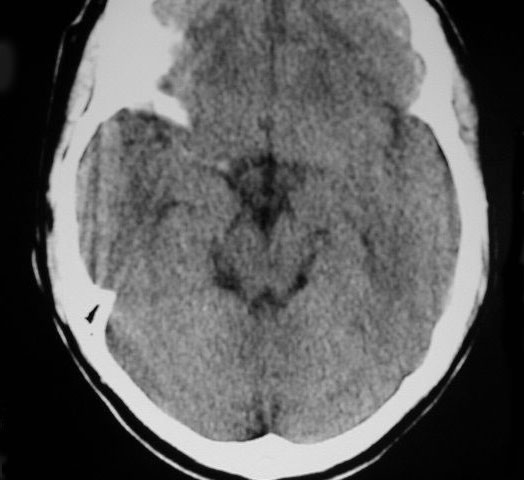

SIGNO DE LA ARTERIA CEREBRAL POSTERIOR HIPERDENSA

A la izquierda, hiperdensidad de ambas arterias cerebrales posteriores flechas). A la derecha, estudio a las 24 horas con infartos de los territorios de ambas cerebrales posteriores.

Es un signo precoz de infarto por obstrucción por trombo o émbolo que afecta a la circulación posterior cerebral. El significado de la imagen es el mismo que el de la arteria cerebral media hiperdensa, más conocido y frecuente.